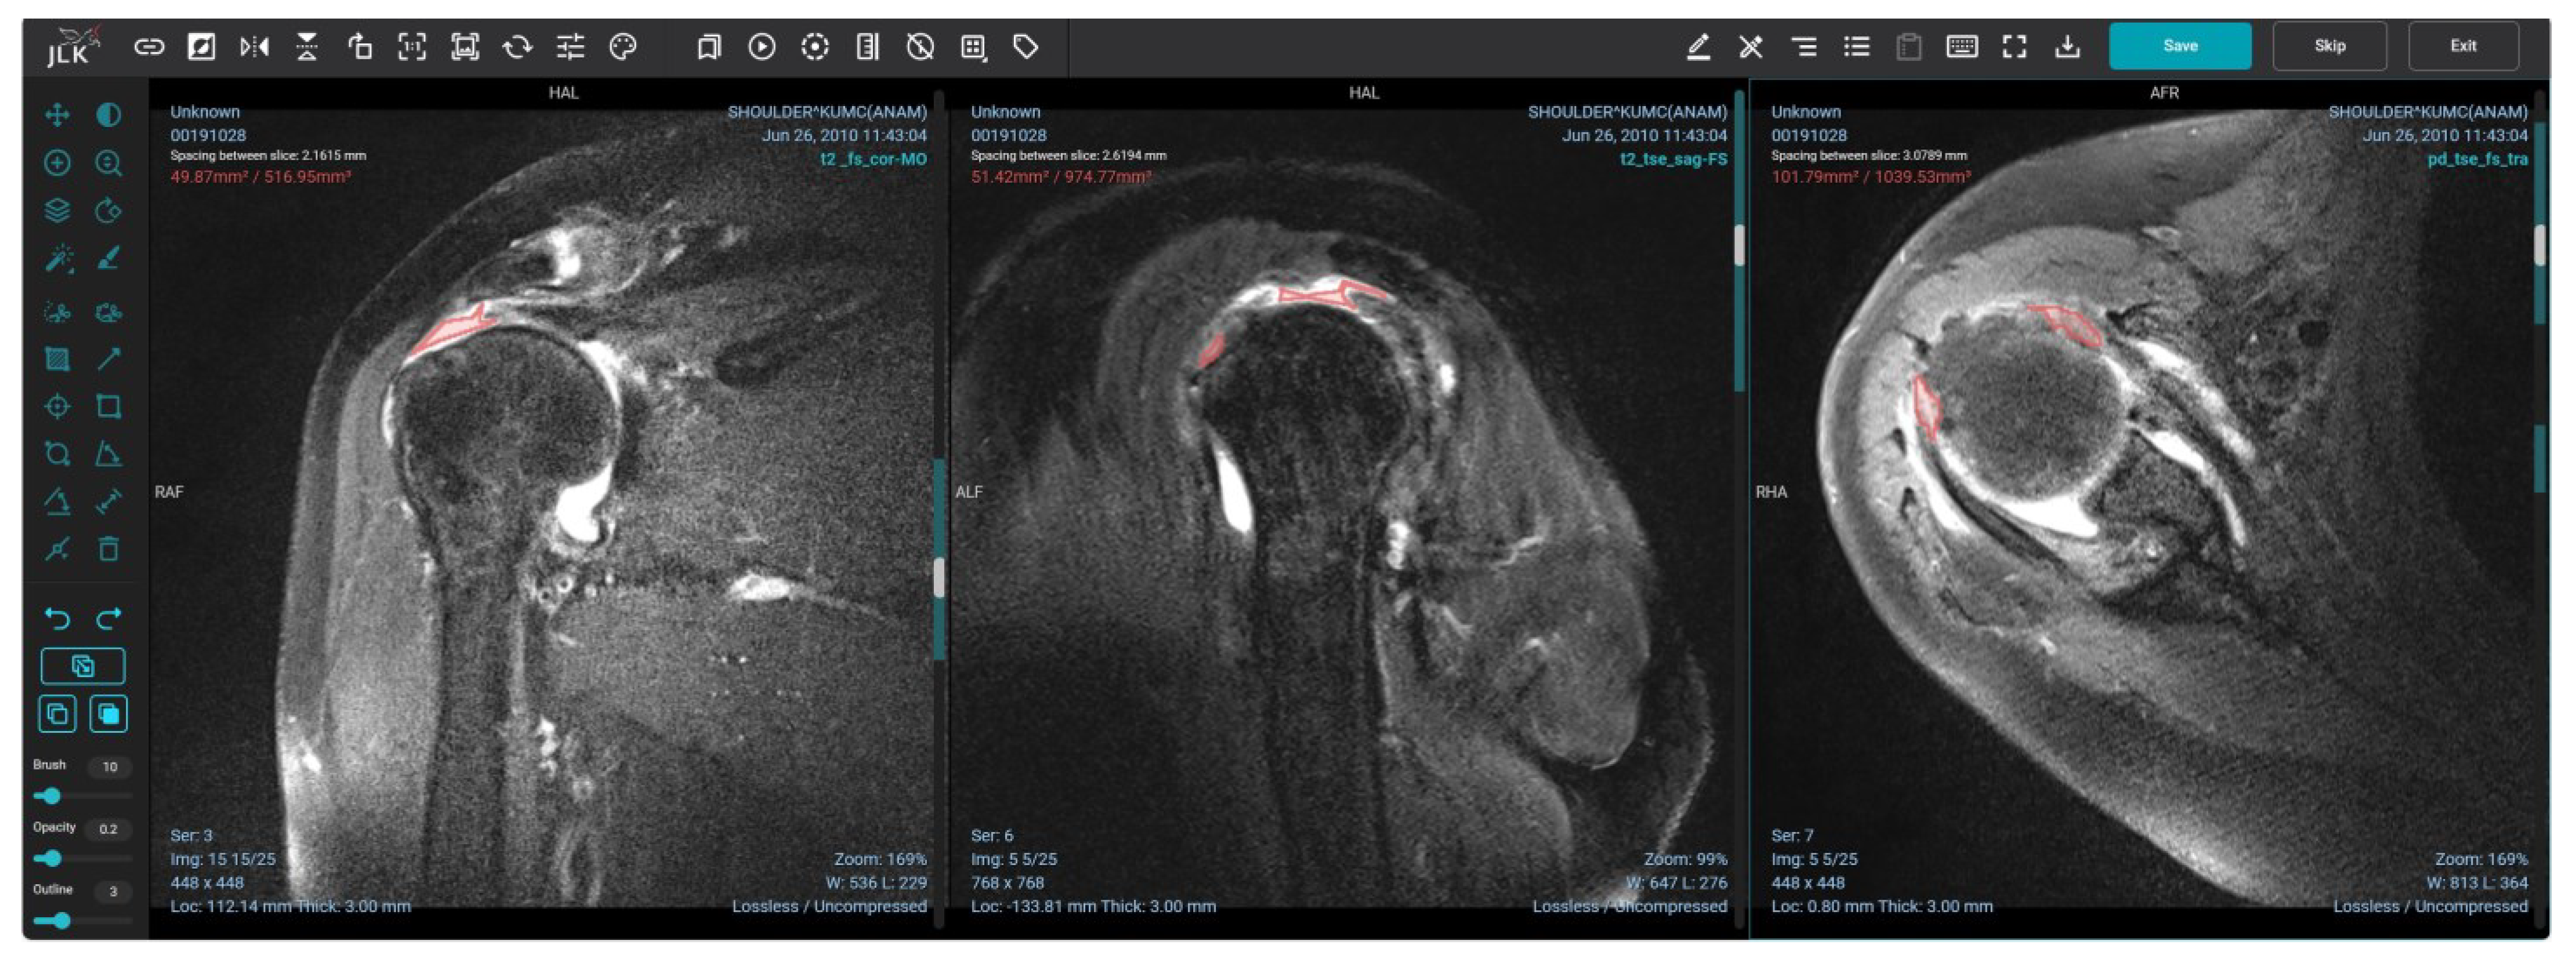

2.1. Image Labeling

2.2. Model Implementation